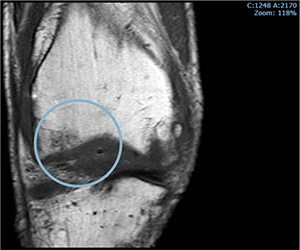

Before starting cell therapy, patients undergo a magnetic resonance imaging (MRI) or computed tomography (CT) scan to assess the condition of the bone and soft tissues of the knee.